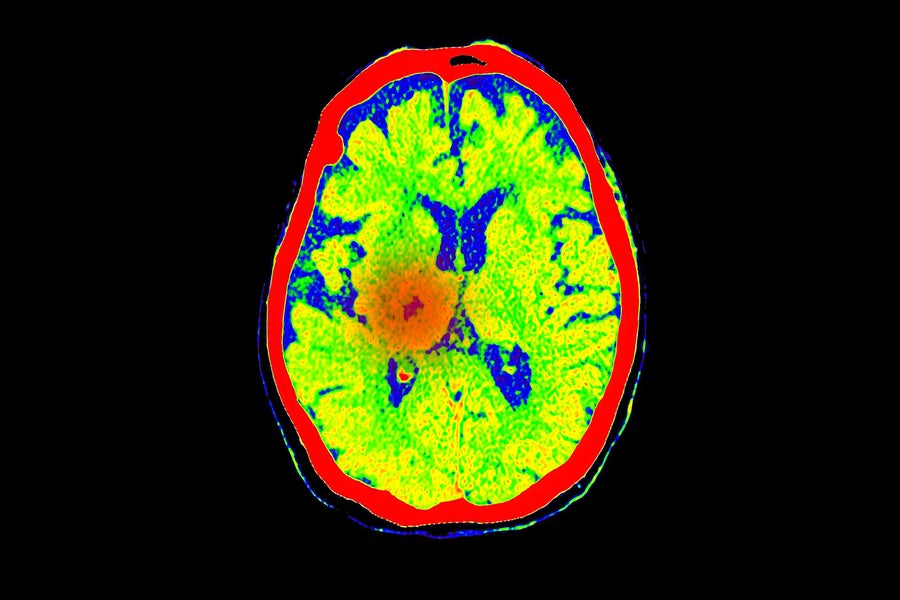

A brain scan shows blood flow at the location of a stroke, a common cause of coma. Mr. Suphachai Praserdumrongchai/Getty Images